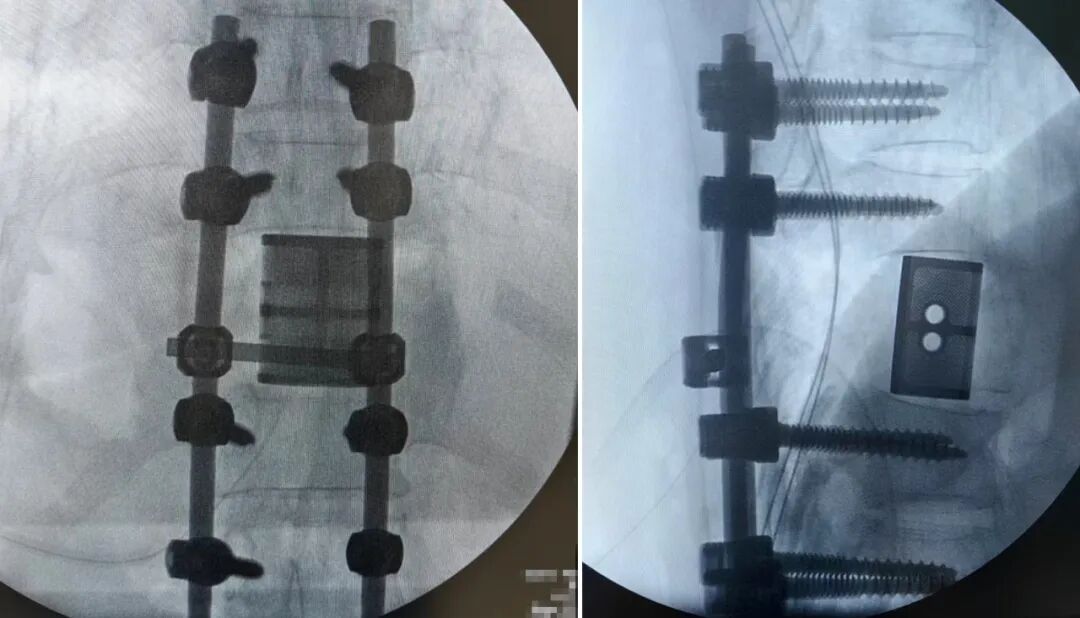

面对挑战,刘邦定带领团队进行了多次深入的术前讨论。他们最终决定为患者施行目前脊柱肿瘤外科领域的前沿术式——“胸10椎体整块切除术” 。该技术旨在将肿瘤及其所在的椎体像一个“信封”一样完整取出,能最大程度降低肿瘤局部复发的几率。为了填补切除后留下的巨大“空缺”,团队采用了最先进的3D打印人工椎体”进行重建。

3D打印人工椎体的优势在于“量体裁衣”。术前,团队根据患者的CT数据,精确打印出与患者原有椎体形态、弧度高度匹配的个性化钛合金人工椎体。这个“私人定制”的假体,能更好地融入原有脊柱序列,实现完美的力学传导与稳定支撑,为术后早期康复奠定了基础。

在充分的术前准备下,由经开骨科团队为患者实施这台高精尖的胸10椎体整块切除及3D打印人工椎体重建术 。手术历时数小时,过程顺利,完整切除了肿瘤,并成功植入3D打印人工椎体,用精密的钉棒系统牢牢固定。